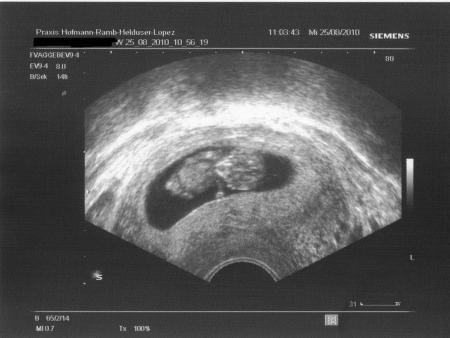

...und ich mag meine FÄ mittlerweile echt nicht mehr leiden! An das lange warten bevor man dran kommt, hab ich mich ja mittlerweile gewöhnt (über eine Stunde!) Aber dann hat sie mich reingebeten ins Untersuchungszimmer und gesagt ich solle mich schonmal untenrum ausziehen, und dann hab ich da halbnackt über 10 Minuten gewartet bis sie kam! Also das find ich echt unverschämt! Ich hab dann meinem Unmut auch mal ein bißchen Luft gemacht, das hat sie nun gar nicht verstanden! Ich würd echt den FA wechseln, aber bei uns in der Stadt sind alle Frauenärzte total überlaufen, und mitten in der Schwangerschaft will ich eigentlich auch nicht wechseln... Nun aber die gute Nachricht, unserem Zwerg gehts super, er ist mittlerweile 40,4 mm groß und strampelt wie ein Weltmeister! Diesmal gabs auch endlich mal ein schönes Foto! Und darüber freu ich mich jetzt und beruhig mich wieder... Achso, ich hab ne leichte Blasenentzündung, aber nix behandlungsbedürftiges. Mehr trinken muß ich!!! LG Steffi

Jetzt hab ich das schöne Foto vergessen!